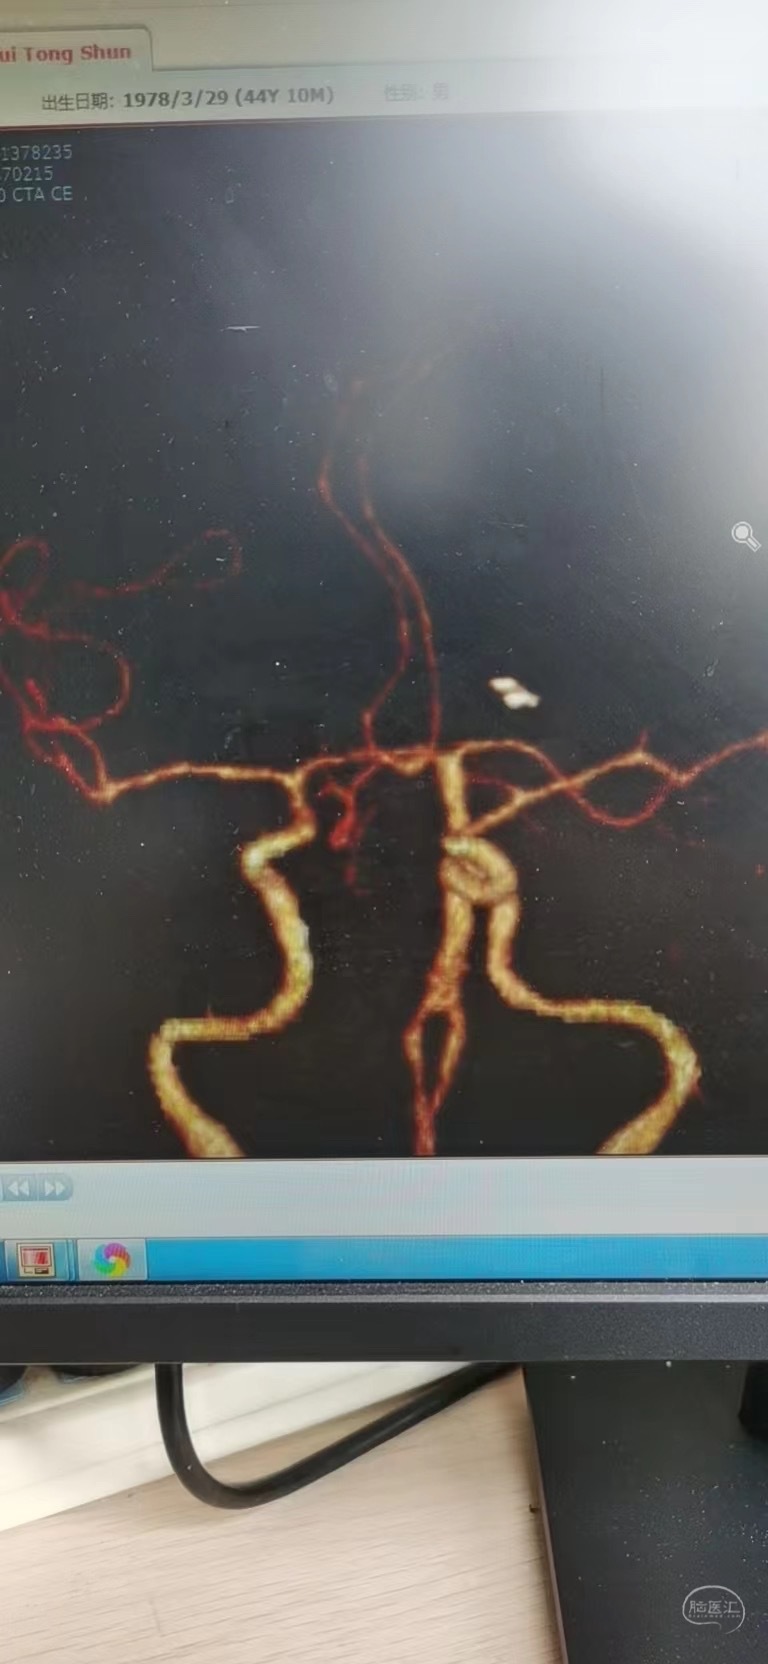

头颅CTA,未发现明显的动脉瘤

3D成像考虑前交通一个微小动脉瘤和一个A2动脉瘤,考虑前交通动脉瘤为破裂动脉瘤